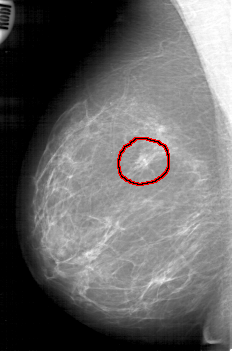

D_4126_1.RIGHT_MLO

RIGHT_MLO LINES 5251 PIXELS_PER_LINE 3466 BITS_PER_PIXEL 12 RESOLUTION 43.5 OVERLAY

FILE: D_4126_1.RIGHT_MLO.OVERLAY

TOTAL_ABNORMALITIES 1

ABNORMALITY 1

LESION_TYPE MASS SHAPE IRREGULAR MARGINS SPICULATED

ASSESSMENT 3

SUBTLETY 4

PATHOLOGY MALIGNANT

TOTAL_OUTLINES 1

BOUNDARY